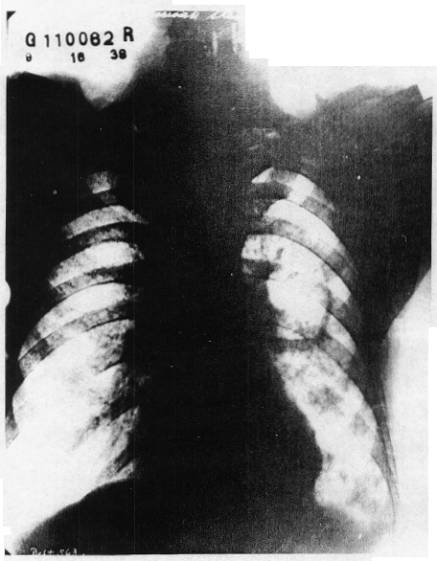

Radiograph I, taken at Herman Keifer Hospital, September 16, 1938.

Radiograph II, taken at our Clinic on October 20, 1938 and showing extension of the tubercular process.

Radiograph I was taken at the Herman Kiefer Hospital on September 16, 1938. Radiograph II was taken at the time he came to our Clinic. A definite increase in the extension of the large cavity and tuberculosis infiltration is seen in this short time. His condition also retrograded constitutionally and with regard to the cough, night sweats, fever, etc.

DR. OMER GRENVILLE HAGUE

“The radiograph of September 16, 1938, is that of a male chest with the bony cage and ribs and collarbones and heart cavity in the middle and diaphragm down there. There are some infiltration shadows in parenchyma, or the active portion of the lung in these areas, in the fourth, fifth, and sixth and seventh interspaces anteriorly and a large cavitation shadow in the mid-lung zone. I am measuring the left lung. That cavity measures 2½ inches by 3¼ inches, a little better than 3¼ inches. The outside measurement of the capsule of the cavity. By a little better than 3¼ inches I mean about 1/8 of an inch more. The reason I am not saying that with certitude is that the upper border of that cavity is very, very thin and very, very faint, but we can see that line that it follows and I would say it would be 3¼ inches at least. That is being very conservative. There is a small fluid level at the bottom of that cavity. There are, also, some heavy hilar shadows, and some thickening of the peri-bronchial trunks; that is, the lymphatics that follow the bronchi and smaller bronchioles. Those shadows indicate repeated infections that have resulted in inflammation and the inflammation has gone on to scarring.